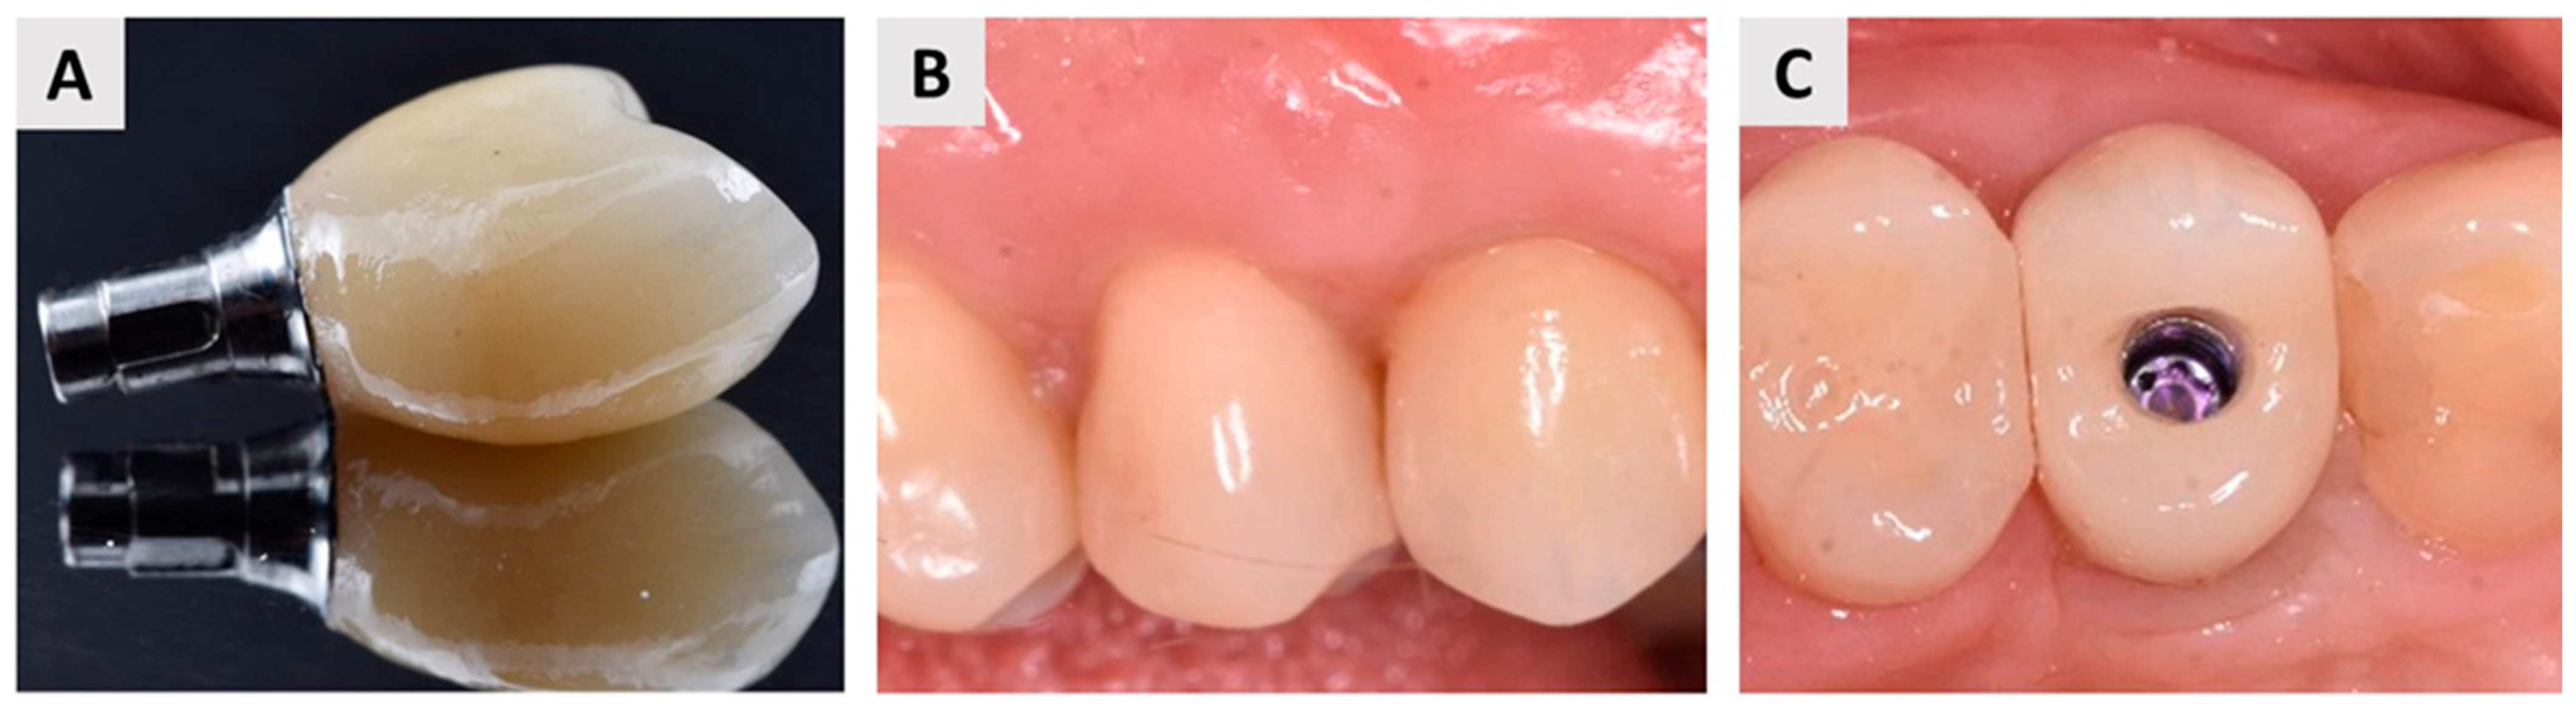

2.5. Dental Implant Placement and Bone Biopsy Harvesting

3.1. Clinical Outcomes